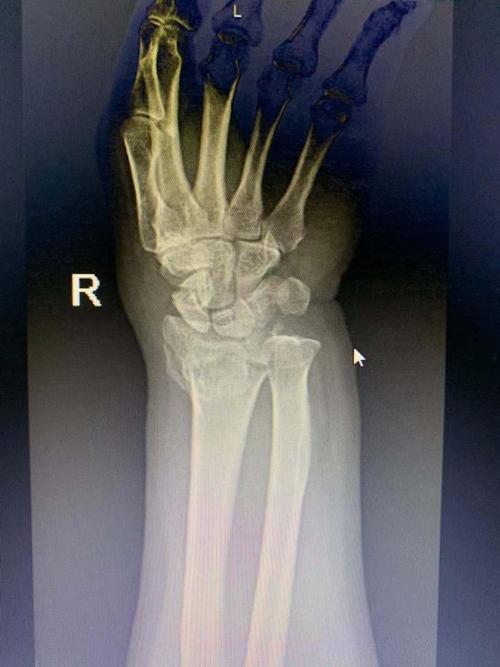

右手手腕骨裂图片

右手手腕骨裂图片,手腕骨折的真实图片

手腕三角骨折了

桡骨远端粉碎性骨折,一定要手术吗?

李医生好,情况是这样子的,我朋友前几天出了场小车祸,右手手腕骨折

点,局部压痛明显,可触及骨擦音及骨右腕关节活动受限,右手各手指感

桡骨远端骨折病人一定要手术治疗吗

手腕骨折的真实图片

手腕骨裂

手腕骨断裂图片

骨裂的片子图片

骨裂x片

骨裂x光片